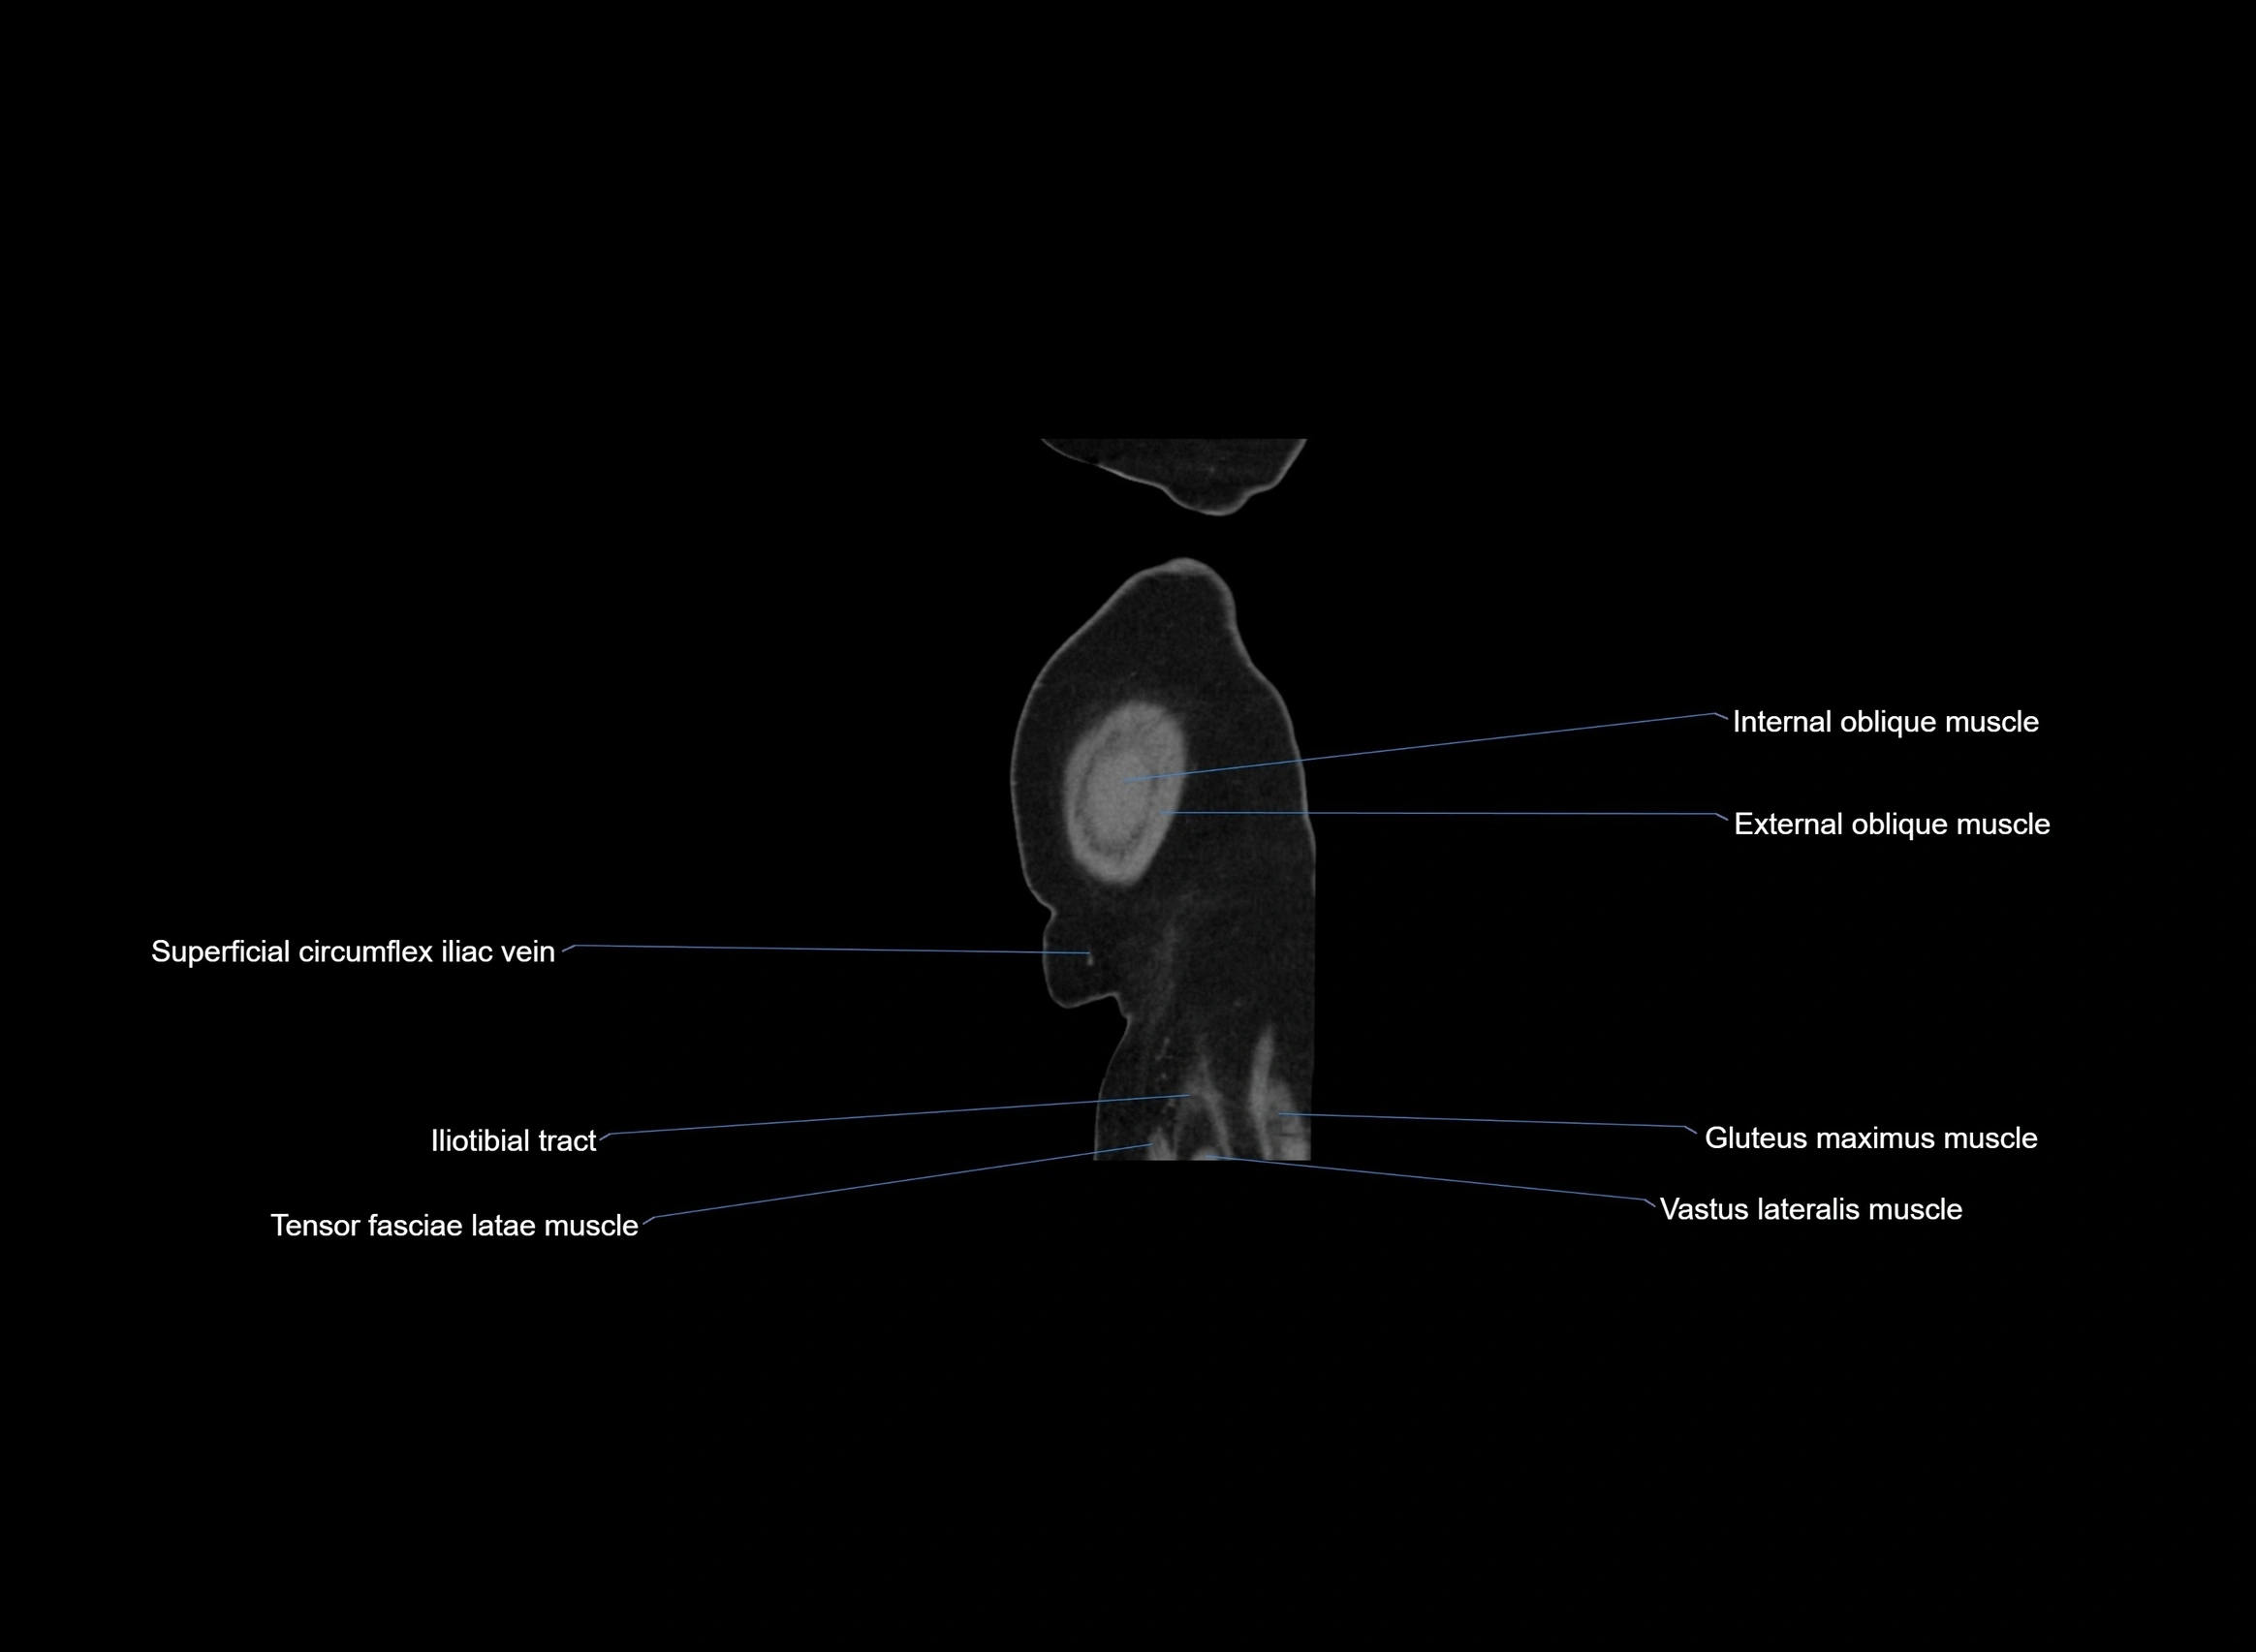

CT images